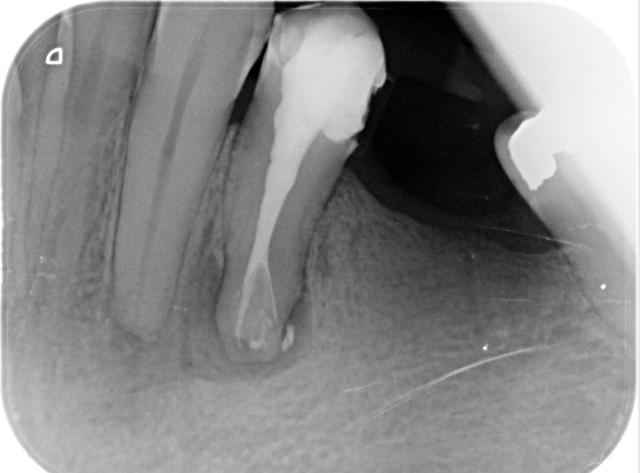

la dent du président

Content de moi.

En fait, c'est la même endo, le radios ont été interverties la finale a été prise sans clamp.... mais l'endo à été faite sous digue.